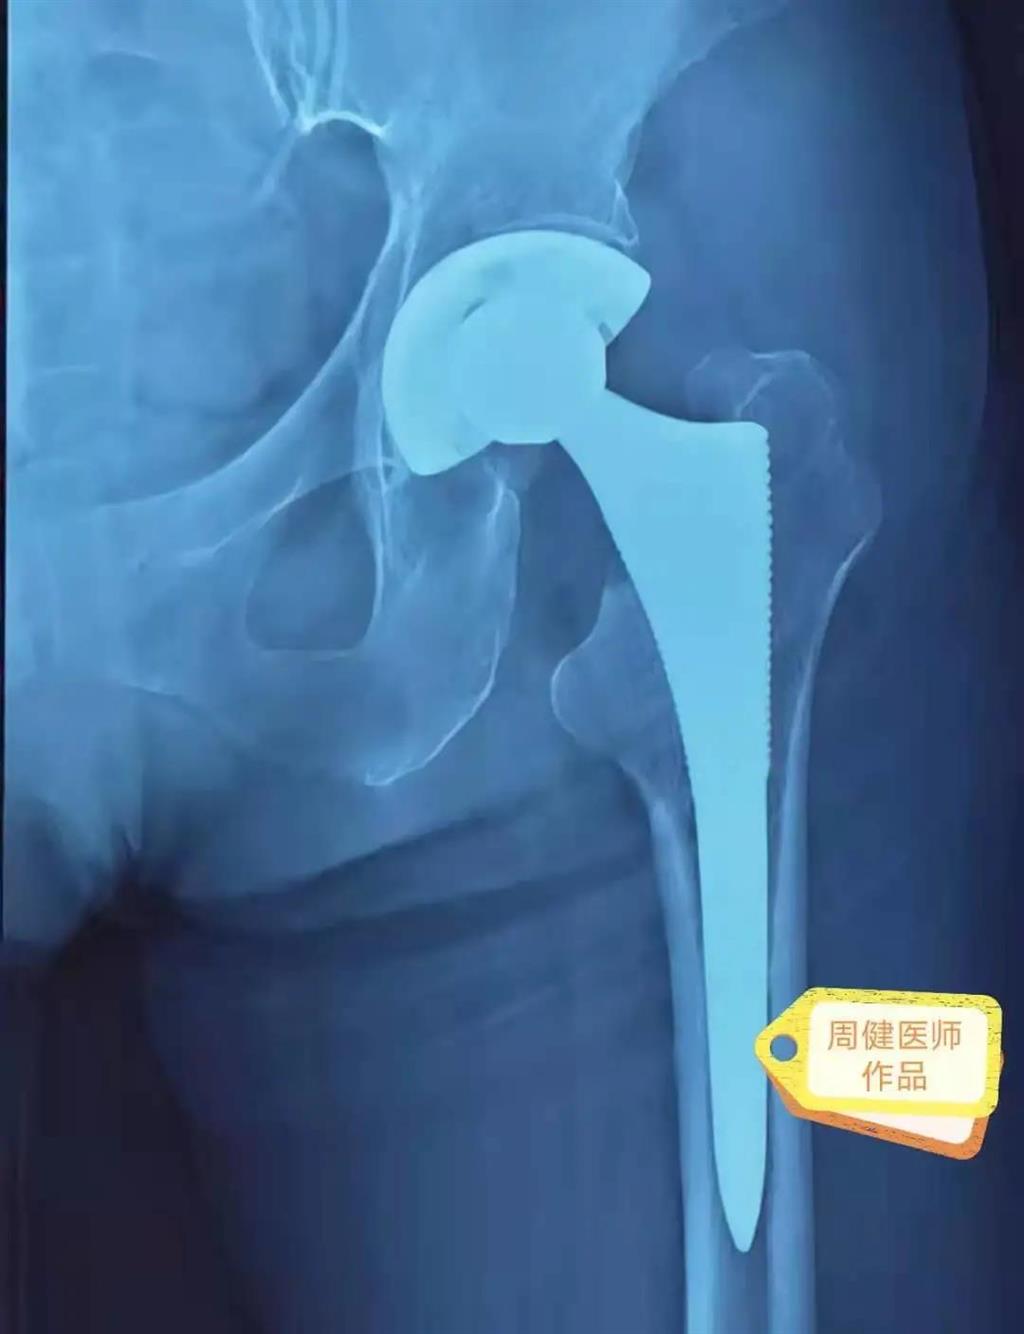

6月30日的“關節置換術”,患者是一位上了年紀的老人,苦于病痛折磨多年的他四處“求醫問藥”,最后在多位專家醫師及病友地力薦下選擇了和平國際醫院,在醫師團隊“偷天換日”般的手術后,老人成功告別了苦纏多年的病痛。

周健說,這場“關節置換術”對于他們團隊而言其實算是比較普通的手術,因為做過很多同類的手術,成功案例繁多,因此在手術操作上有較多地實操經驗。“不過話雖如此,作為醫生我們對于每一場手術都會全力以赴,這是為醫者的職責也是義務。”